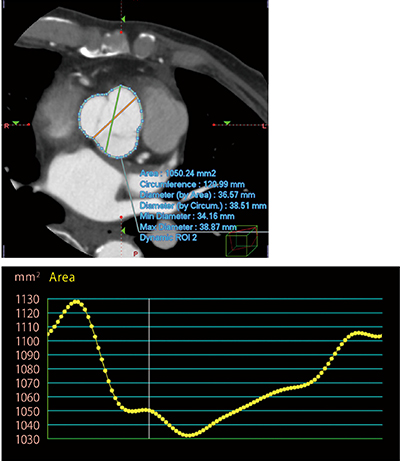

われわれの開発したバルサルバ洞の伸展性評価は、冠動脈CTで得られた心電図R-R間隔の10%ごとの元データを、PhyZiodynamics処理により10フェーズから100フェーズに増やしたデータを使用する。PhyZiodynamicsの特徴は、予測補間技術を使って、基の位相データを2〜10倍の位相データに再編し、時間分解能を向上させたイメージングを可能とすることである。それと同時に、位相の異なる画像のROI輪郭の自動追随を可能とする“Dynamic ROI機能”が開発された。PhyZiodynamicsはすべてのボクセルデータをトラッキングしており、全フェーズにおける位置情報を持っているため、自動追従が可能となっている。Dynamic ROI機能により、バルサルバ洞の周囲長および面積を心拍動に合わせて追従し、心周期を通して自動計測することが可能となった(図3)。

図3 Dynamic ROI機能によるバルサルバ洞計測

グラフ横軸は時間、縦軸はバルサルバ洞面積